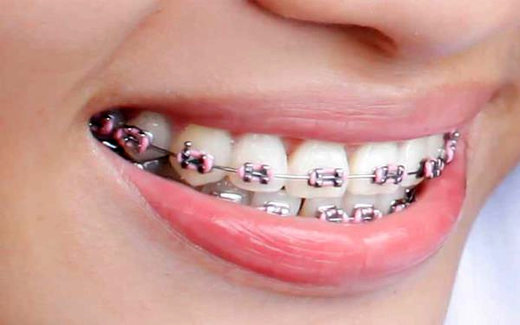

ایسنا/ با شروع درمان ارتودنسی، مراقبت از دندان و لثه بیش از همیشه اهمیت پیدا میکند، براکتها و سیمهای ارتودنسی علاوه بر اصلاح فرم دندانها، میتوانند محل تجمع باکتریها و باقیماندههای غذایی باشند و در صورت رعایت نکردن بهداشت، مشکلاتی مانند پوسیدگی، التهاب لثه و بوی بد دهان ایجاد کنند.

وی توضیح داد: براکتها، سیمها و تجهیزات ارتودنسی باعث تجمع بیشتر پلاک و باقیماندههای غذایی میشوند و مسواک زدن را دشوار میکنند، این موضوع احتمال پوسیدگی دندان، التهاب لثه و بوی بد دهان را افزایش میدهد و میتواند روند درمان را تحت تأثیر قرار دهد.

مویدی شایعترین مشکلات دهان و لثه در بیماران ارتودنسی را شامل پوسیدگی دندان، التهاب و خونریزی لثه، ایجاد لکههای سفید روی مینای دندان و بوی بد دهان دانست و گفت: برای پیشگیری، بیماران باید پس از هر وعده غذایی مسواک بزنند، روزانه از نخ دندان مخصوص ارتودنسی استفاده کنند و بهطور منظم به دندانپزشک مراجعه نمایند.

عضو هیأت علمی دانشگاه علوم پزشکی شیراز درباره روش صحیح مسواک زدن در دوران ارتودنسی، بیان کرد: استفاده از مسواکهای مخصوص با شیار وسط و مسواکهای بیندندانی (interdental) توصیه میشود تا اطراف براکتها بهتر تمیز شود، هنگام مسواک زدن، حرکات دایرهای کوچک و پاک کردن کامل نواحی بالا و پایین سیمها و براکتها اهمیت دارد.